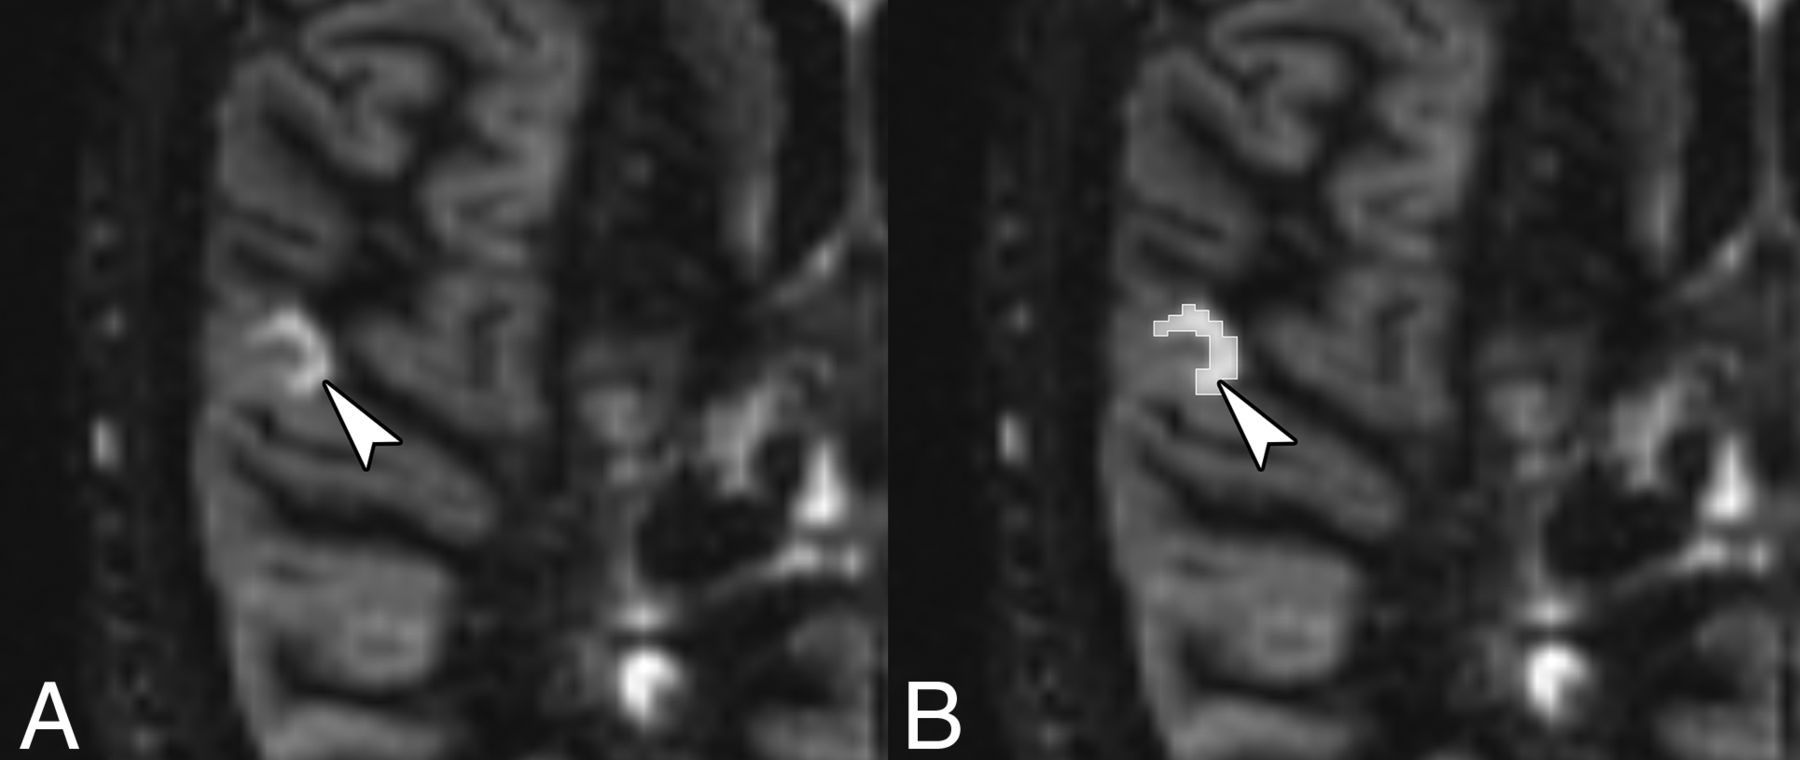

iCLs were detected in 55/71 (77%) patients. An example of a purely iCL is shown in Fig 1. On the basis of iCL status, patients were divided into groups positive and negative for iCL. Clinical and imaging data were compared between these 2 groups. No difference in the disease phenotype (RRMS, SPMS, PPMS) was detected between groups (P = .11). Patients with iCLs were older (P = .003) and had longer disease duration (P < .001) and the highest EDSS scores (P = .02). Results are shown in the Table 1.

An example of a purely intracortical lesion (arrowhead) (A) on the DIR MR image and its manual segmentation using 3D Slicer (B).